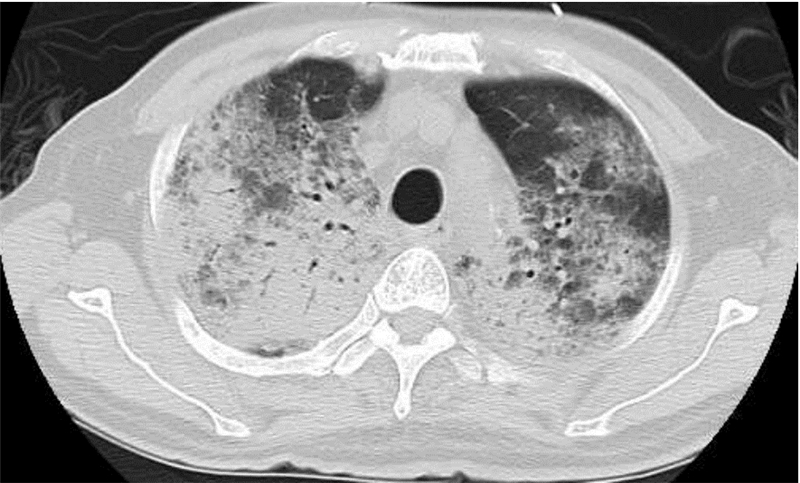

例3 患者,男,50岁,6年前确诊为多发性骨髓瘤(IgG型,κ轻链,Ⅲ期A组),经VAD方案化疗后缓解,2年前复发,给予PCD等方案化疗后再次缓解。2011年8月26日予硼替左米+马法兰预处理化疗,9月1日回输“O”型自体造血干细胞345 mL,有核细胞数8.09×108/kg,CD34+细胞3.39×106/kg,过程顺利,移植后13 d中性粒细胞计数>0.5×109/L,移植后15 d血小板计数>20×109/L,过程顺利。出院后定期随诊,病情稳定。移植后8个月余出现发热(体温39.0 ℃)、咳嗽、咳少量白色黏痰,腰痛伴双下肢麻木,双肺未闻及明显干湿性啰音,查血常规:白细胞 6.1×109/L,血红蛋白 91 g/L,血小板 145×109/L;C反应蛋白174.4 mg/L;胸部CT:两肺纤维增殖灶,两侧胸膜反应。骨髓常规示原始浆细胞32%;免疫球蛋白IgG 3 150 mg/L;免疫固相电泳示IgG、κ轻链阳性。诊断:呼吸道感染、多发性骨髓瘤(复发)。广谱抗感染及抗真菌治疗半个月后出现咯血、胸闷、呼吸困难,皮下血氧饱和度81%,双肺可闻及湿啰音及散在干啰音;查血常规:血常规 6.7×109/L,血红蛋白 58 g/L,血小板 42×109/L;凝血功能:PT 15.8 s,APTT 40 s,Fg 5.1 g/L;胸部CT:两肺内可见多发片状模糊阴影,边缘不清,内密度不均匀,其内可见通气支气管影,以两上肺为著。诊断DAH。予无创呼吸机供氧,甲强龙针500 mg 静推每8 h一次及抗感染治疗,9 d后因呼吸衰竭而死亡。

| 图 2 例3肺部CT:两肺内可见多发片状模糊阴影 |